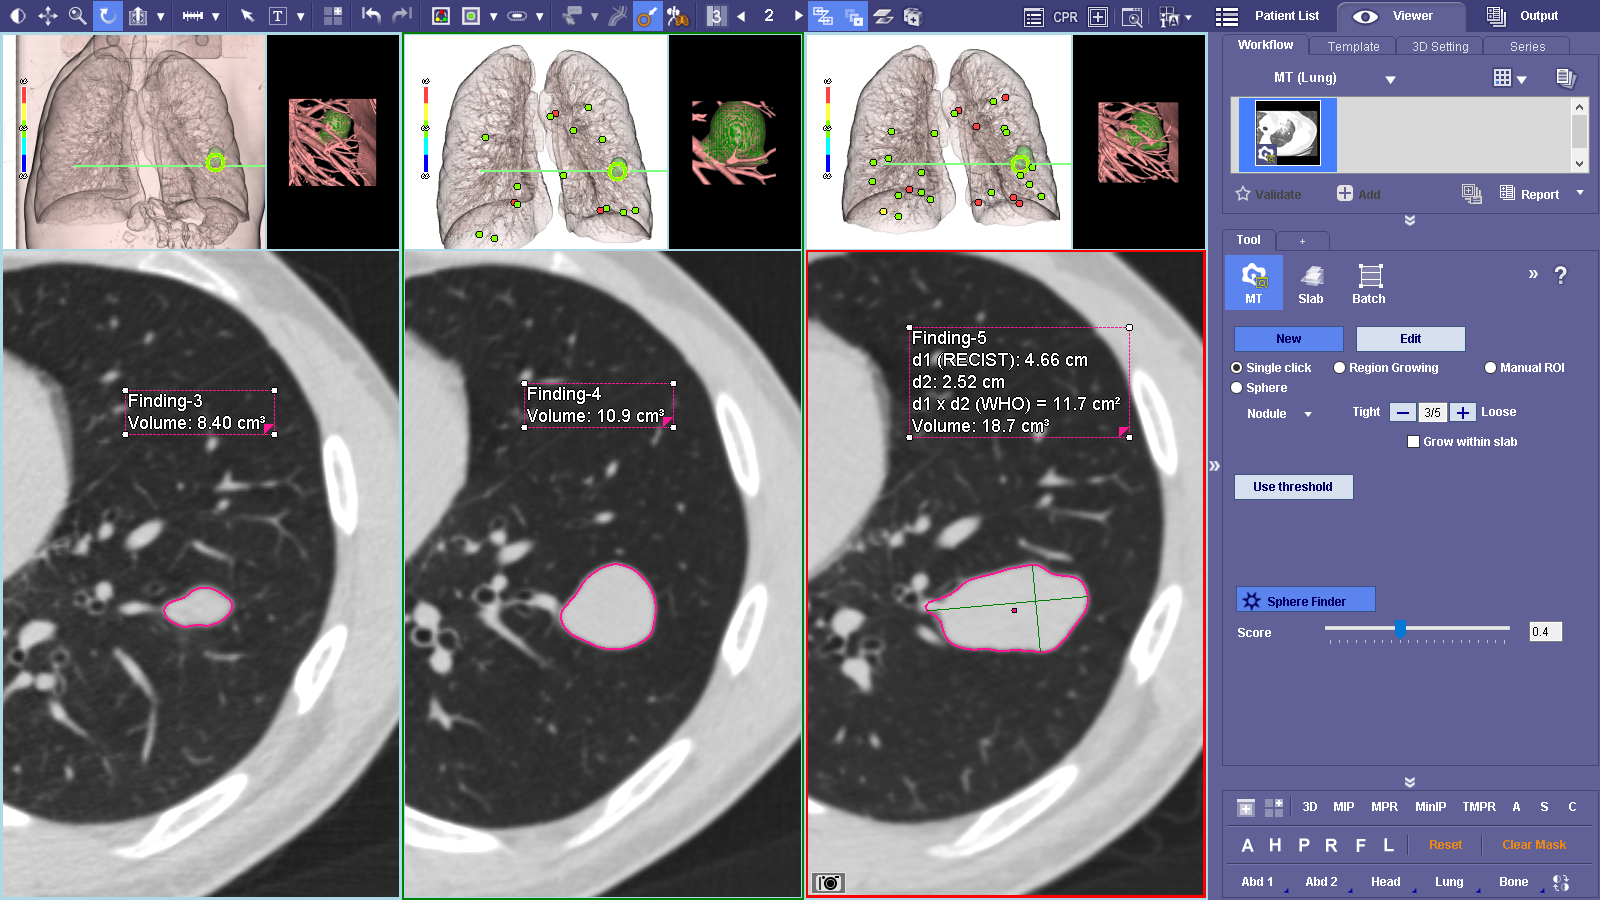

MT Lung workflow is a comprehensive lung analysis tool used to segment, analyze and track lung lesions over the course of time. SphereFinder allows a second look as the software helps identify spherical areas of interest. The Findings Viewer aids in tracking, classifying and measuring confirmed areas of interest. The Measurement Tracking feature tracks confirmed measurements over time.

MT Lung workflow is a comprehensive lung analysis tool used to segment, analyze and track lung lesions over the course of time. SphereFinder allows a second look as the software helps identify spherical areas of interest. The Findings Viewer aids in tracking, classifying and measuring confirmed areas of interest. The Measurement Tracking feature tracks confirmed measurements over time.

Supporta criteri come LRADS®1/01 Le misurazioni e le classificazioni vengono visualizzate su Findings Viewer.

Criteri di monitoraggio come LRADS®1/01

Visualizzazione dei grafici del visualizzatore dei risultati in base ai criteri scelti.

I risultati possono essere assegnati dal menu contestuale.